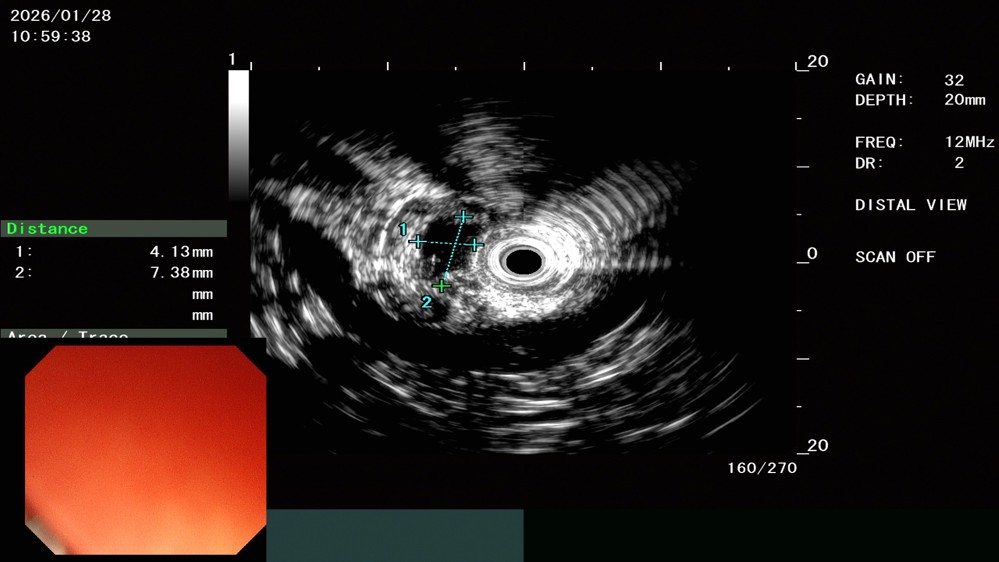

为此,张先生在医院接受了超声内镜检查。脾胃病科副主任医师景洪海检查发现,该隆起来源于黏膜下层,呈偏低回声,内部结构不均,但周围胃壁层次清晰正常。结合其顶端有凹陷的特征,超声内镜明确提示“异位胰腺考虑”。

除了上消化道,超声肠镜在下消化道疾病的诊断中同样扮演着不可替代的角色。52岁的王大爷肠镜发现直肠有一可疑病变。经超声确认病灶源于黏膜深层,呈均匀低回声,边界清晰,直肠黏膜下隆起,考虑神经内分泌肿瘤,需要内镜下治疗。